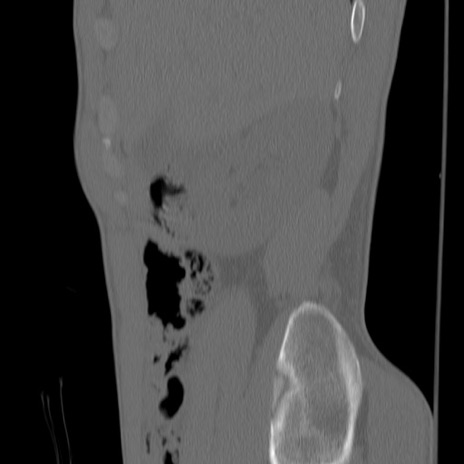

症例3 腰椎CT(矢状断像)

【症例】30歳代男性

【主訴】腰痛

【現病歴】本日旅行先で観光中に、友人と衝突し転倒し受傷。

【身体所見】麻痺なし、右下腿内側前面外側、左下腿内側に知覚鈍麻・しびれ

異常所見と診断は?

腰椎CT